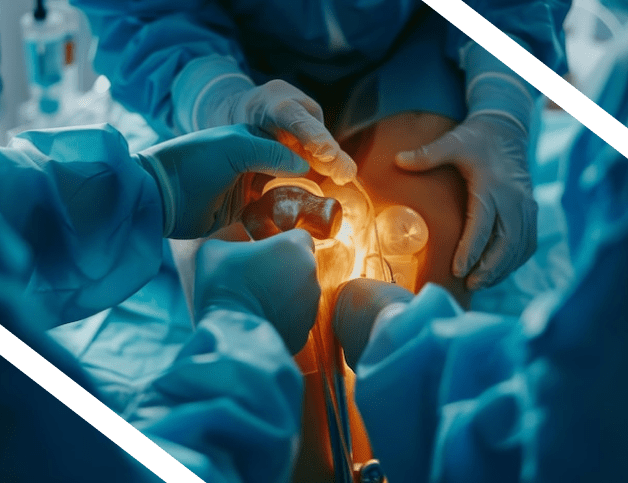

The India Anterior Hip Foundation Course (IAHF 2026) is a focused, high-impact surgical education program designed to deliver true mastery of the Direct Anterior Approach (DAA).

This course brings together national and international faculty to provide precision-based learning, structured modules, and expert mentorship.

IAHF 2026 is committed to accelerating your learning curve and enhancing your confidence in modern hip arthroplasty techniques.